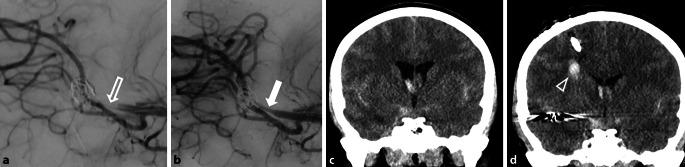

Tirofiban is administered for the treatment of aneurysms in cases of thromboembolic complications, as well as in cases of acute stenting or flow-diverter implantation required within the scope of aneurysm treatment. We aimed to investigate the efficacy and safety of tirofiban in this group of patients.

A total of 105 patients were included, with 61% women and 39% men (mean age = 53 years, IQR: 44-60 years). Sixty-seven patients underwent emergency aneurysm treatment, and thirty-eight were treated electively. Hemorrhagic events occurred in 22% (15/67) of the patients treated acutely, with 7.46% (5/67) exhibiting symptoms. Patients undergoing elective aneurysm treatment experienced no hemorrhagic events (p = 0.002). Among the 35 patients who required an external ventricular drain (EVD), 22.86% (8/35) developed EVD-related hemorrhages; however, none were symptomatic (p = 0.007). Of the five patients who required a craniotomy, two experienced significant bleeding, and one experienced non-significant craniotomy-related bleeding (p = 0.20).

Tirofiban may be safe for use during peri-interventional complications or emergency stenting in aneurysm treatment. However, caution is necessary when craniotomy is required. In elective aneurysm treatments, administering Tirofiban in response to periprocedural complications appears to be safe.